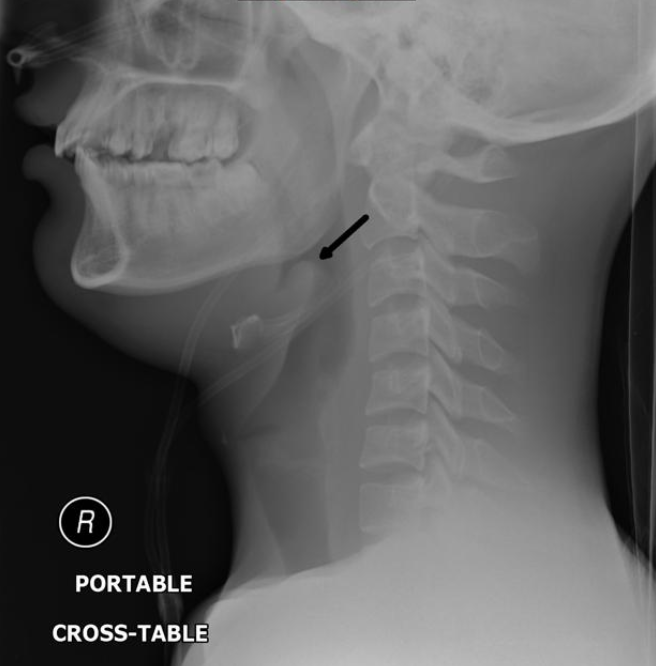

Epiglottitis is classically a clinical diagnosis, and emergent consultation of ENT and anesthesia should not be delayed pending imaging as the airway can rapidly decompensate. If the patient can tolerate it, a lateral neck X-ray can show a "thumbprint" sign, which shows an enlarged epiglottis. If the patient is stable, a CT of the neck should also be performed.

Figure: Thumbprint sign in epiglottitis. Image courtesy of Andrew Ho. Used under the Creative Commons Non-Commercial Attribution, Sharealike license.